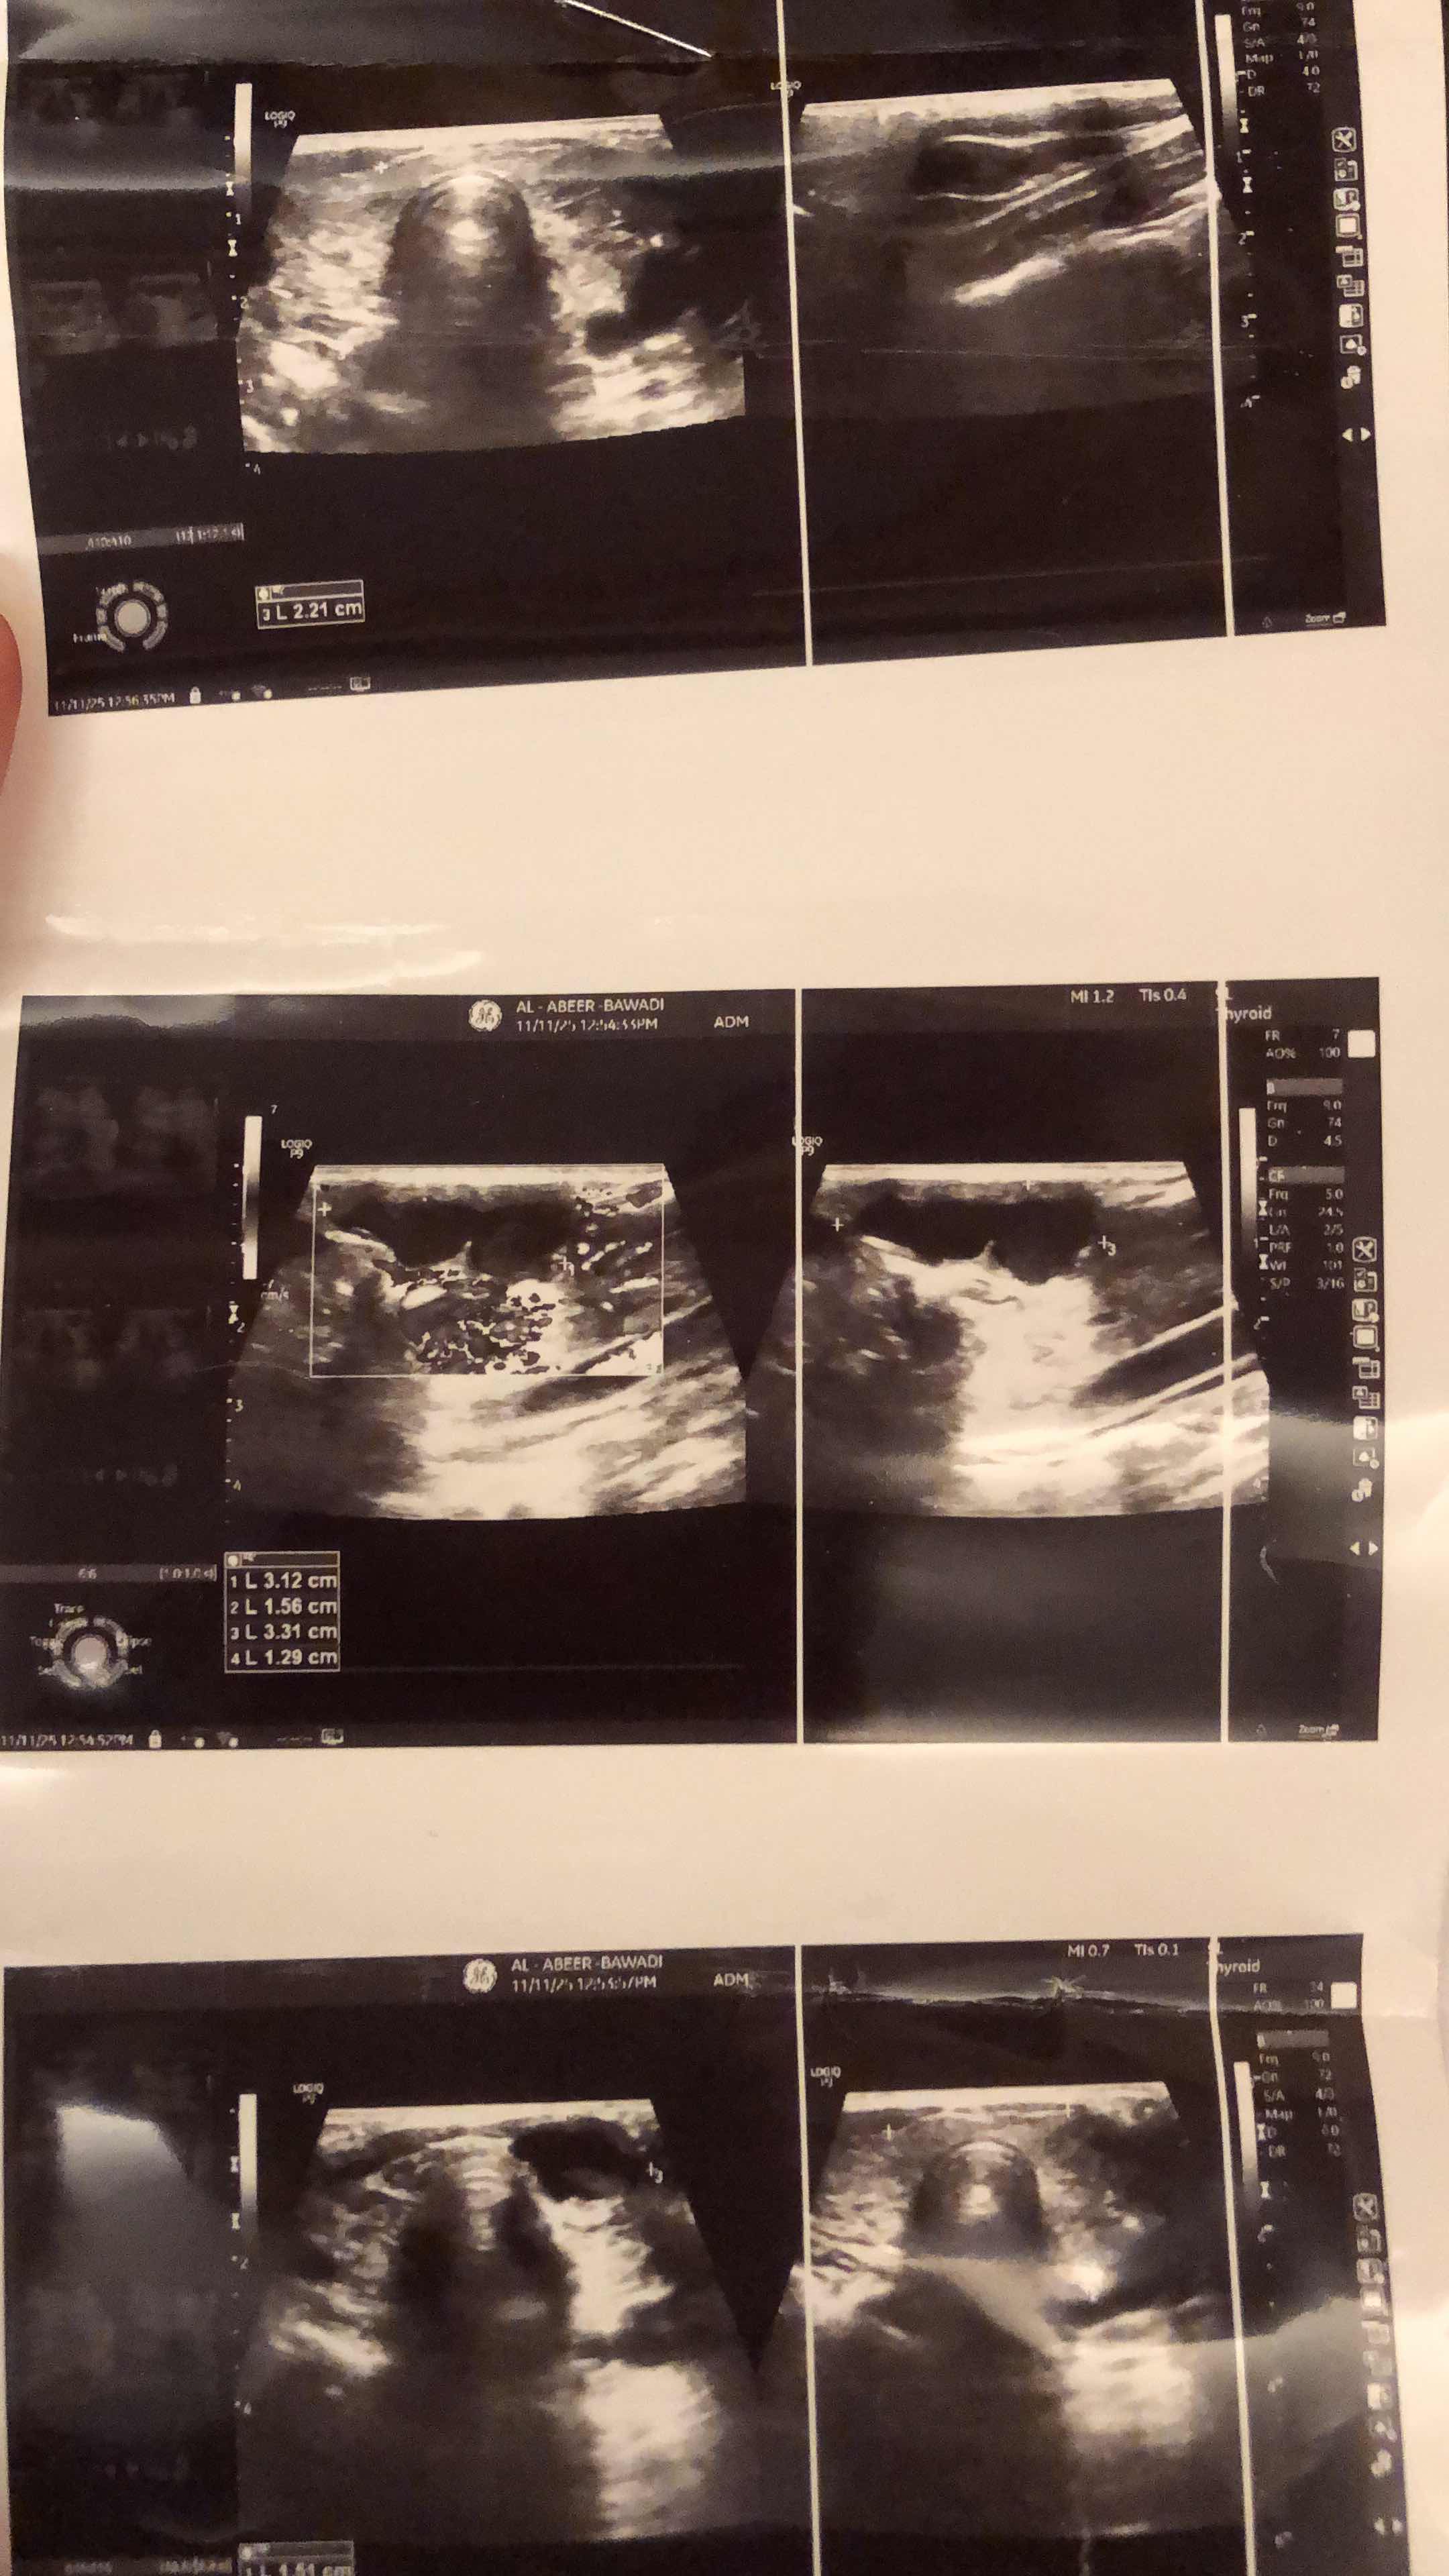

انا عندي الرقبه في زي الورم مع الجوانب يمين ويسار واسخن واتعب منها وتألمني مره رحت كذا مستشفى وكل دكتور...